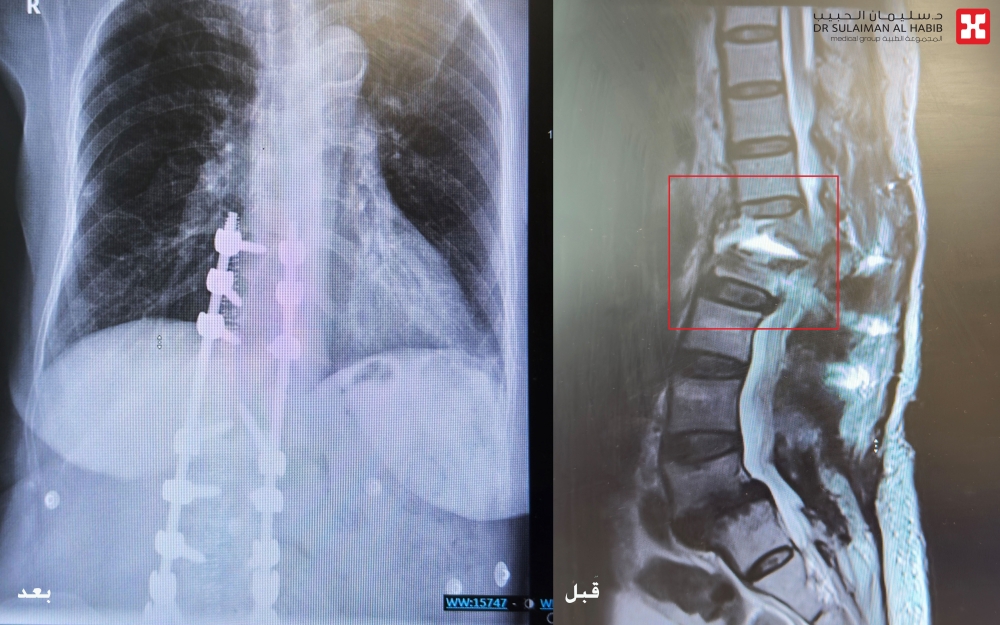

شهد مستشفى الدكتور سليمان الحبيب بالخبر، إجراء عملية معقدة ومتقدمة لمراجعة “سبعينية” تعرضت لكسر حاد وانفصال في العمود الفقري، جراء إصابتها بانزلاق غضروفي قبل سنوات، وتعقدت حالتها بعد محاولتها للعلاج وخضوعها لــ “5” عمليات في مستشفيات أخرى داخل وخارج المملكة، وقد انتهى بها الحال مصابة بشلل في الأطراف السفلية. ذكر ذلك الدكتور حسام الحبيب استشاري طب وجراحة العمود الفقري والمخ والأعصاب، رئيس الفريق الطبي المعالج، الحاصل على الزمالة الكندية.

والذي أضاف بأن المراجعة حضرت للعيادة على كرسي متحرك، حيث تم الاستماع إلى شكواها والإطلاع على ملفها الطبي وإجراء الفحص السريري، وتبين أنها فقدت القدرة على الوقوف والمشي منذ شهر، وذلك بعد خضوعها لخمس عمليات سابقة في العمود الفقري، موضحاً أن فحوصات الرنين المغناطيسي (M.R.I) والتصوير المقطعي (C.T. Scan) والأشعة السينية الرقمية (Digital X-Rays) والتحاليل المخبرية، أثبتت إصابتها بكسر وانفصال الفقرة الأولى القطنية عن العمود الفقري، وحدوث ضغط شديد على الحبل الشوكي والأعصاب، كما تبين من التحاليل وجود هشاشة عظام من الدرجة المتقدمة.

مشيرًا إلى أن العملية استغرقت 4 ساعات متواصلة تحت التخدير العام، وتم فيها استخدام تقنيات المجهر الجراحي والملاحة العصبية وأجهزة مراقبة الأعصاب، حيث تم فتح الظهر وإزالة كامل التثبيتات السابقة والمسامير الغير مستقرة، تبع ذلك معالجة تشوه العمود الفقري حول الكسر بالفقرة القطنية الأولى، واستخدام مسامير خاصة متوافقة مع مرضى هشاشة العظام تتميز بقدرة تثبيت عالية.